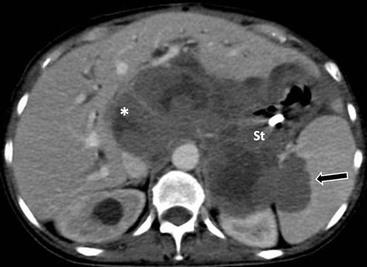

In acute pancreatitis, extravasated pancreatic enzymes may dissect along the mesenteric pathways.1 An extrapancreatic acute fluid collection may spread along the root of transverse mesocolon and, at times, of small-bowel mesentery and extend along the vessels to the vasa recta of the transverse colon and small bowel (Fig. 30-8).5